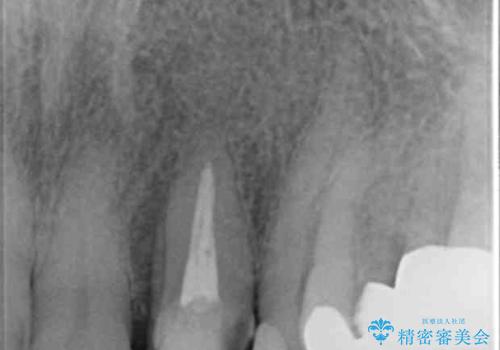

根管治療が為されたまま、クラウンの装着が行われず変色し審美障害を来している状態です。

維持を保つためのファイバーコア築盛を行い、精密なジルコニアクラウン製作を行います。